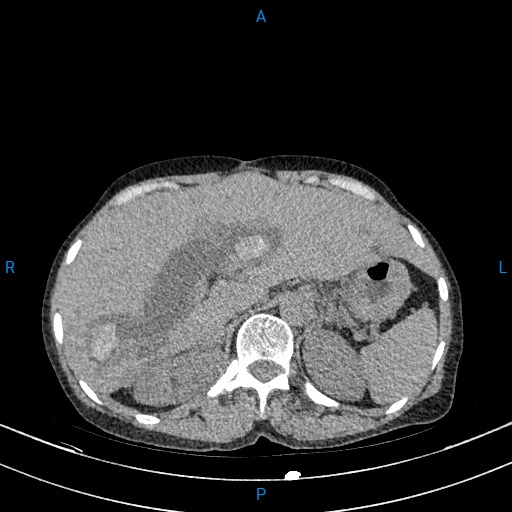

Vừa qua, các Bác sĩ Bệnh viện Đa khoa Hải Dương đã thực hiện phẫu thuật cho một trường hợp bệnh nhân Trương Thị T. (62 tuổi) ở Hòa Bình, Xã Thanh Miện, Thành phố Hải Phòng có tiền sử mổ sỏi mật 3 lần. Gần đây, Bệnh nhân ở nhà mệt mỏi, ăn uống kém, đau âm ỉ vùng thượng vị và hạ sườn phải, vàng da, củng mạc vàng nên đến viện kiểm tra. Qua thăm khám và chụp cắt lớp vi tính, các Bác sĩ thấy đường mật trong ngoài gan giãn nhiều, ống mật chủ giãn 27mm có nhiều sỏi, sỏi lớn nhất kích thước 38x 31mm, sỏi lớn đường mật gan phải kích thước 22x17mm, sỏi lớn đường mật gan trái 26x15mm. Bệnh nhân được chẩn đoán nhiễm trùng đường mật do sỏi. Hội chẩn đánh giá bệnh nhân có sỏi ống mật chủ to, nhiều sỏi đường mật trong gan, chỉ định phẫu thuật mở ống mật chủ lấy sỏi và nội soi đường mật trong mổ ống mềm kết hợp tán laser sỏi đường mật trong gan.

Hình chụp cắt lớp vi tính sỏi ống mật chủ của bệnh nhân T.